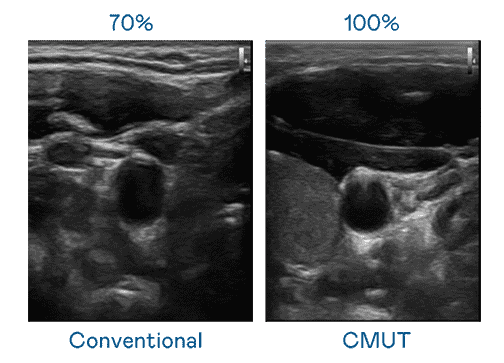

CMUT 技术是一种用电容式微机电元件来产生超音波讯号的技术。。与传统 PZT 压电式技术相比,,,CMUT 频宽增加 30%,,,,更宽频的超音波讯号让影像解析度大幅提升,,,,是实现高影像品质医疗超音波扫描、、、、促进精准医疗发展的关键技术。。。

大频宽带来超清晰影像

超音波影像的解析度高低,,首先取决于探头能发出的讯号频宽。。。。口袋牛店 CMUT 可提供高清晰的超音波讯号,,,提供高频宽、、、高灵敏度、、影像纹理细节更高的超音波影像,,,协助医护人员缩短影像判读时间及利用精准的医疗影像进行诊断。。。